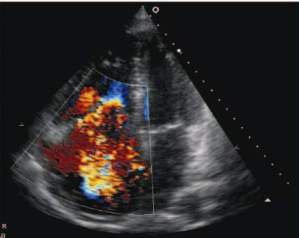

Obrázky 1 a 3 ukazují nález octreoscanu před operací a po radikální operaci, obrázky 2 a 4 ukazují totéž na CT. Obrázek 5 demonstruje echokar biografický nález významné trikuspidální regurgitace, obrázek 6 ukazuje normalizaci onkomarkerů sérového chromograninu A a obrázek 7 normalizaci hodnot odpadů 5 - hydroxyindoloctové kyseliny (5 - HIOK) v moči. Hodnoty CA 125 byly v celém průběhu v normě.

Echokardiografický nález trikuspidální regurgitace